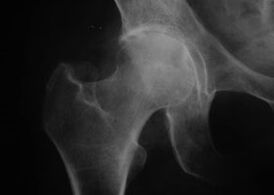

Coxatroza, artroza articulației șoldului

Cu această boală, se observă un tablou clinic clasic al artrozei.

Primul simptom al coxartrozei este disconfortul la nivelul articulației șoldului după activitatea fizică.

Odată cu coxartroza progresivă, apare durerea, rigiditatea și mobilitatea limitată.

Pacienții cu o formă severă de coxartroză cruță membrul afectat, evitând călcarea pe el și, în timp ce staționează, aleg poziții în care durerea este cel mai puțin resimțită.